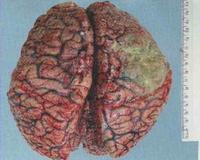

Менингит. Это воспаление мягкой мозговой оболочки и паутинной оболочки, возникающее при заражении бактериальными, вирусными или грибковыми агентами. В клиническую триаду входят сильные головные боли в области лба и висков, многократная рвота без тошноты и повышение температуры тела выше 38 ° С. Диагностика патологии предполагает общий и микробиологический анализ спинномозговой жидкости, томографию головного мозга. В программу лечения входят этиотропные препараты (антибиотики, противовирусные средства, иммуноглобулины), патогенетическая и симптоматическая терапия. Для предотвращения осложнений подбирается комплексная программа восстановления.

При воспалении менингеальных мембран происходит дистрофическое повреждение нейронов и окружающих клеток, ухудшается кровоснабжение тканей мозга и возникает тяжелая гипоксия. Гнойный лептоменингит характеризуется развитием фиброзного воспаления, резкими нарушениями динамики ликвора. В сложных случаях возможно вовлечение тканей мозга в процесс формирования менингоэнцефалита.